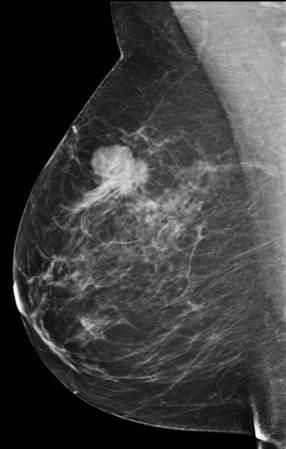

Ung thư vú

» Thông tin: Nữ giới – 55 tuổi.

» Lâm sàng: Khối tuyến vú.